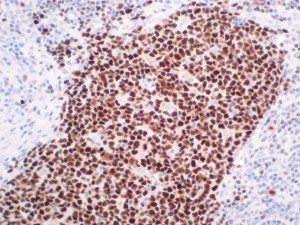

The first cytokines released are interleukin 1β (IL-1β) and tumor necrosis factor-α (TNF-α), which attract a variety of circulating white blood cells (WBCs) to the infection site, including neutrophils, monocytes, macrophages, and natural killer (NK) cells. This response, along with the antipathogenic chemicals released by these cells (i.e., complement), comprise the innate immune response. These cells directly attack the invading pathogen and also release additional cytokines, chief among them interleukin-1 and 6 (IL-6). IL-6 is essential for invoking the adaptive immune response, which calls T-cells, B-cells, and T helper (Th) cells to the infection site. IL-6 also stimulates further recruitment, proliferation and activation of macrophages.

It is the ICU physician who is most likely to witness one of the deadliest manifestations of the abnormal immunological response, the cytokine storm syndrome (CSS). This response is also referred to by some as the cytokine release syndrome (CRS). CSS is characterized by continuous activation and expansion of macrophage and lymphocyte populations, which secrete large amounts of cytokines, causing the cytokine storm. This massive cytokine release is akin to hemophagocytic lymphohistiocytosis (HLH) disease, a syndrome characterized by initial unchecked and persistent activation of cytotoxic T lymphocytes and NK cells.